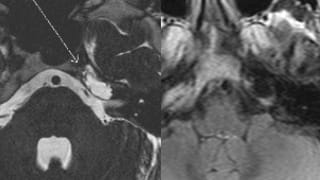

MRI of the Internal Auditory Canals with and without Intravenous Contrast

High-resolution MR imaging of the internal auditory canals and petrous temporal bones, as well as MR imaging of the entire brain, with and without intravenous contrast.

Thorough evaluation of the brain stem, 7th and 8th cranial nerves, membranous labyrinths, and temporal bones.

- Benign or malignant masses (vestibulocochlear schwannoma, facial schwannoma, facial nerve hemangioma, meningioma, metastatic disease, brain stem glioma, perineural spread of parotid malignancy, arachnoid cyst, epidermoid cyst, cholesteatoma, cholesterol granuloma, middle ear adenoma, paraganglioma, endolymphatic sac tumor, neurofibromatosis type II)

- Vascular lesions (vascular loop, aneurysm, vascular malformation)